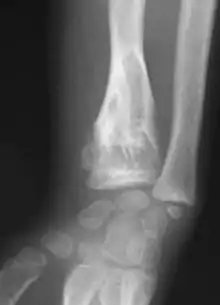

The disease consists of the growth multiple enchondromas which usually develop in early childhood. The growth of these enchondromas usually stops after skeletal maturation.[4] The affected extremity is shortened (asymmetric dwarfism) and sometimes bowed due to epiphyseal fusion anomalies. Bone lesions generally present as cellular during childhood and become more solitary over time. People with Ollier disease are prone to breaking bones (fractures) and normally have swollen, aching limbs. However, many cases of solitary enchondromata go unnoticed due to lack of symptoms. Enchondromas are commonly found in the phalanges, metacarpal, and metatarsal bones in patients of Ollier disease due to the affinity of enchondromas to long tubular bones such as the femur and humerus. A unilateral distribution of bone lesions is usually observed but bilateral distributions or a singular extremity can occur as well. Approximately a third of the cases show some form of physical deformities of bowing or abnormal limb lengthening.

Abnormal bone growth such as shortening or thickening and deformity may be observed in patients of Ollier disease. These bone lesions are visible at birth using radiography but are usually not screened or examined for until clinical manifestations present during early childhood. However, some patients may exhibit no signs of any symptoms.[1] One study found thirteen to be the mean age of diagnosis in patients with Ollier disease. In an X-ray, there would normally be the presence of several homogeneous lesions of an oval or elongated shape with bone edges that are slightly thickened.[3] With age, these lesions may calcify and appear as diffusely minute spots or stippled. Fan-like septations or streaks would be indicative of the presence of several enchondromas. Early detection and consistent and repeated monitoring is important in order to prevent and treat any potential bone neoplasms.